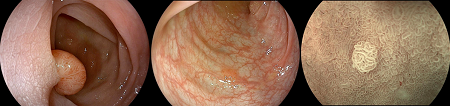

▲清晰成像助力精準診斷

基于開立醫(yī)療強大的多光譜成像技術,HD-580系列具備WL/EWL/SFI/VIST四種成像模式,能夠同時適應快速篩查和精準診斷的需求。同時,HD-580系列繼續(xù)全面提升光學染色效果。基于開立醫(yī)療特色的光電復合染色成像方法,SFI模式更能凸顯黏膜淺層血管,適于在中遠距離下快速、大范圍進行病灶快速篩查。VIST模式能清晰凸顯淺層黏膜血管和中層黏膜血管,適于在近距離下進行病灶精確觀察和精準診斷。上述兩種特色的成像功能下,均可設置三種不同的成像效果,以適應不同鏡體及部位的觀察需求。